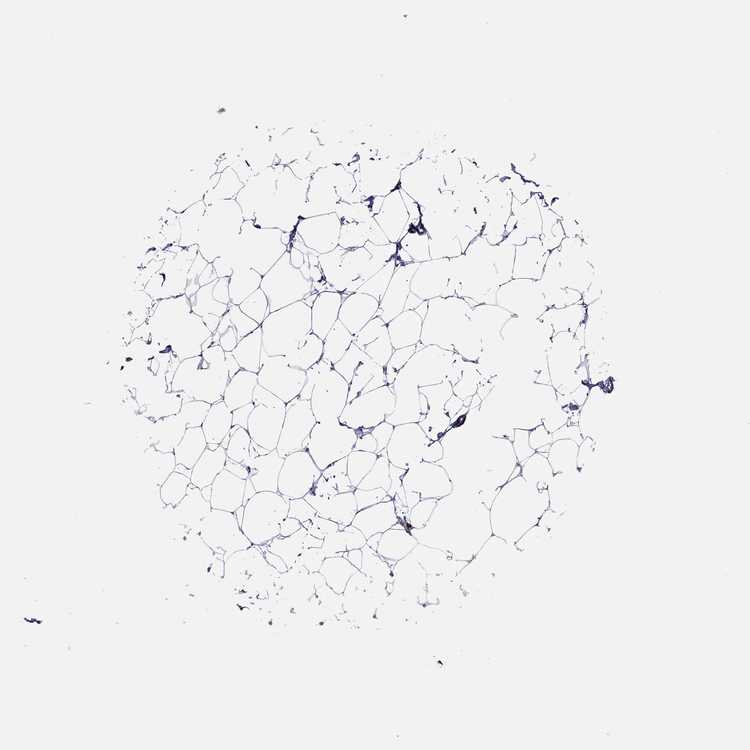

BREAST - Antibody stainingi

Antibody staining in the annotated cell types in the current human tissue is reported as not detected, low, medium, or high, based on conventional immunohistochemistry profiling in selected tissues. This score is based on the combination of the staining intensity and fraction of stained cells.

Each image is clickable and will lead to virtual microscopy that enables deeper exploration of all samples and also displays staining intensity scores, fraction scores and subcellular localization as well as patient and tissue information for each sample.

Antibody HPA038355

Adipocytes Not detected

Glandular cells Medium

Myoepithelial cells Not detected